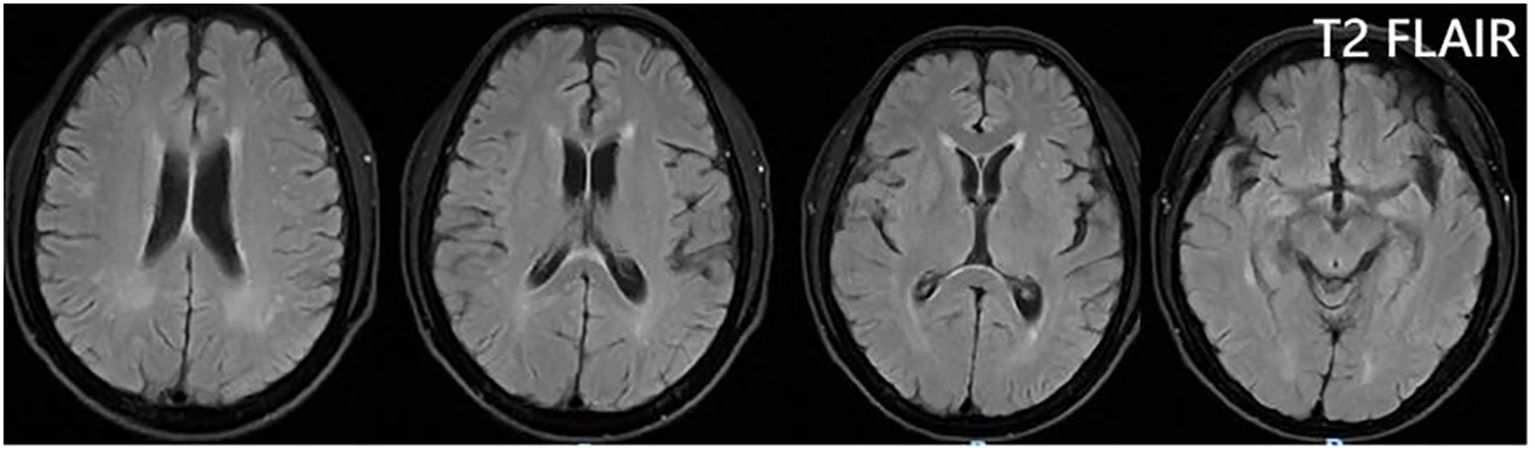

From 8 April, the clinical symptoms demonstrated progressive improvement, marked by the patient’s transition from stupor to drowsiness on a consciousness scale. By 16 April the patient was alert and attentive to these questions. A high dose of methylprednisolone was administered for 5 days and the dose was subsequently decreased gradually. Dehydration was implemented to reduce intracranial pressure. Another lumbar puncture was performed on the tenth day of admission (15 April). CSF analysis revealed normal glucose levels with elevated protein (0.89 g/L). The leukocyte count in the CSF was 78×106/L, representing a significant decrease compared to the WBC count in the CSF on 4 April. MOG-IgG in the CSF and serum was negative, and GFAP-IgG in the CSF was negative. The serum IgG decreased to 3.21 g/L, reflecting a 56% reduction compared with the previous serum IgG level. Another cranial MRI was performed on 3 April. The T2 FLAIR showed multiple hyperintensities in the posterior horn of the lateral ventricle, medial temporal lobe, and temporal cortex (Figures 2, 3). After tapering the corticosteroid therapy, the patient was transitioned to oral administration. He was discharged from the hospital on 18 April with a notable improvement in symptoms. At the one-month post-discharge outpatient follow-up visit, all psychiatric symptoms had disappeared completely. Treatment included low-dose oral steroids and mycophenolate mofetil. Three months after discharge, the patient underwent cranial MRI, which showed that the multiple hyperintensities in the medial temporal lobe and temporal cortex had decreased (Figure 4). Ten months after the patient’s initial presentation, no symptoms except for cognitive impairment were observed, and no drug-related adverse reactions were reported, with the patient reporting an “irritable mood” (MMSE: 26, MOCA: 13, HAMA: 5, HAMD: 1). The impaired dimensions included visual-spatial function, execution, and memory.

Figure 4

Four axial T2 TLAIR MRI brain scans showing different cross-sections. Each image reveals varying levels of gray and white matter, with attention to ventricular structures and cortical details.

Figure 4. T2 FLAIR showing that the multiple hyperintensities in the medial temporal lobe and temporal cortex became small three months after discharge.